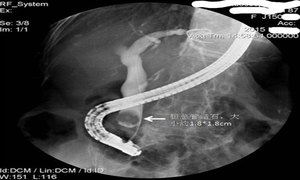

B型超声波可显示胆囊或肝胆管内有增强光团,有声影。X线腹部摄片常可见结石阴影。胆囊胆道造影可显示结石阴影。